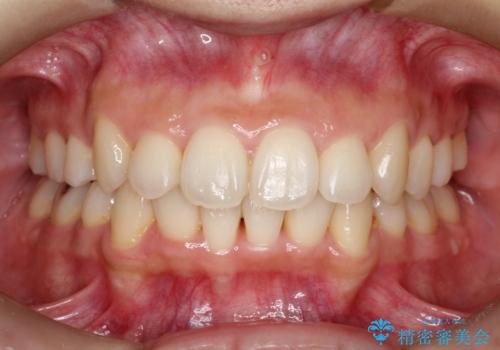

再矯正症例 前歯のガタガタと噛み合わせのズレをマウスピースで治した症例